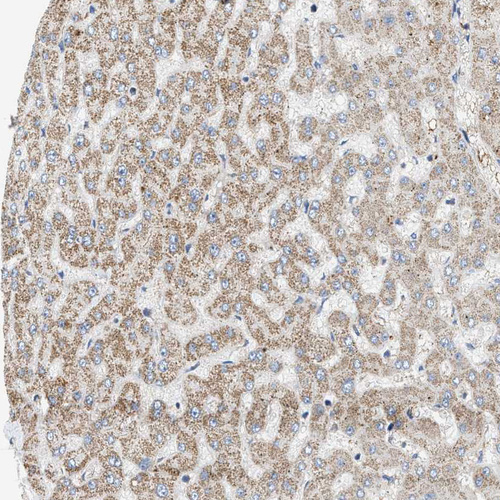

Immunohistochemical staining of human heart muscle, kidney, liver and testis using Anti-OXSM antibody HPA021300 (A) shows similar protein distribution across tissues to independent antibody HPA021293 (B).